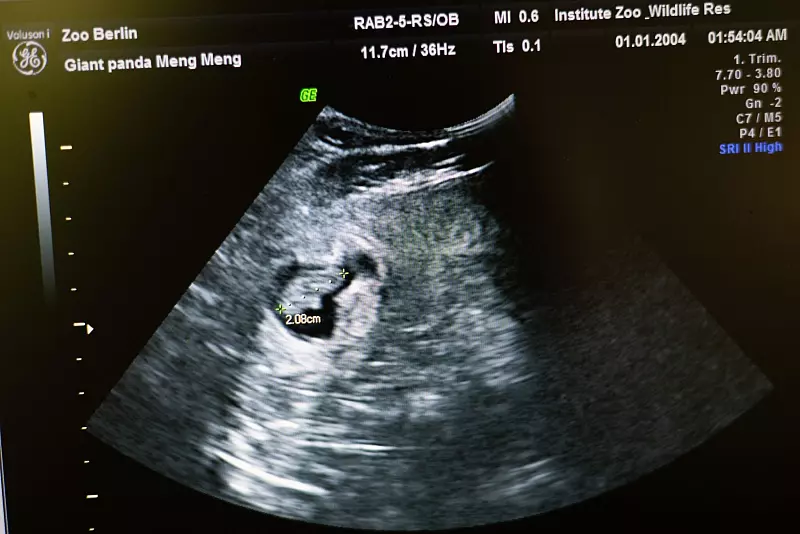

Einer der beiden Embryonen auf dem Bildschirm eines Ultraschallgerätes. - © Sebastian Gollnow/dpa

Einer der beiden Embryonen auf dem Bildschirm eines Ultraschallgerätes. (© Sebastian Gollnow/dpa)

Knapp drei Zentimeter sind sie groß und sie machen sehr viele sehr glücklich: Die Rede ist vom Panda-Nachwuchs im Berliner Zoo, der am Sonntag zum ersten Mal im Ultraschall nachgewiesen wurde. Denn das Weibchen Meng Meng ist wieder trächtig - mit Zwillingen.

Am Sonntag seien die kleinen Panda-Embryos 2,5 Zentimeter groß gewesen, zwei Tage später sogar schon 2,9 Zentimeter, erzählt der Tierarzt Thomas Hildebrandt, der die Abteilung Reproduktionsmanagement am Leibniz-Institut für Zoo- und Wildtierforschung (IZW) in Berlin leitet. Auch der Zwilling, der am Sonntag nicht so gut auf dem Ultraschall zu sehen war, hat sich heute gezeigt: Er ist gewachsen. Das Wachstum verläuft rasant. Bis zur Geburt in 12 bis 20 Tagen erreicht der Nachwuchs die Größe von Meerschweinchen.